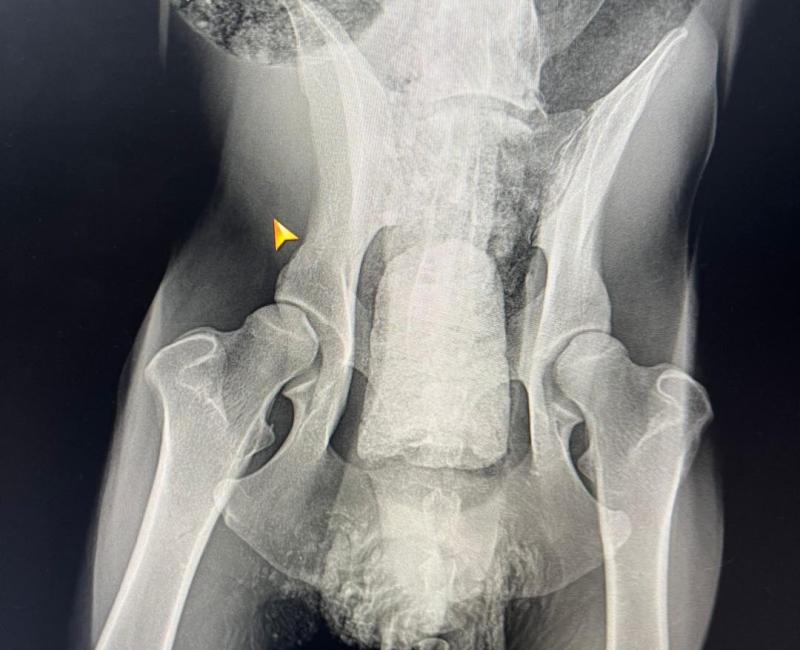

Terry desde siempre tuvo muchos problemas digestivos, por desgracia, de la noche a la mañana se paralizó internamente. Lamentablemente hay cosas que no podemos controlar y que suceden sin más, dejándote un vacío lleno de dudas, preguntas y sentimientos de culpa porque no se puede evitar el buscar explicaciones aunque en el fondo sepamos que la vida es injusta a veces y tienes que asumirlo.